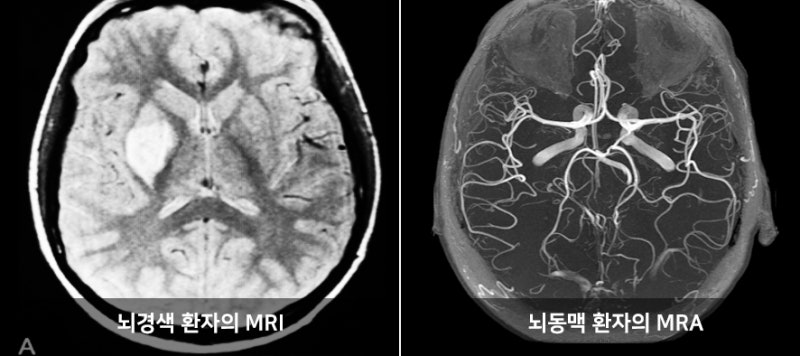

MRI(자기 공명 영상)은 강력한 자기장과 라디오파를 이용하여 체내 조직의 이미지를 생성하는 기술입니다. MRI는 연부 조직, 즉 뇌, spinal cord, 근육, 그리고 다양한 내장 장기 등을 상세하게 볼 수 있는 특징이 있습니다. 주로 신경계, 근골격계 및 종양 연구의 진단 도구로 사용됩니다.

반면에 MRA(자기 공명 혈관 영상)는 MRI의 일종으로, 혈관의 이미지를 생성하는 데 초점을 맞추고 있습니다. 이는 혈관의 구조 및 흐름을 평가하는 데 유용하며, 주로 심혈관 질환의 진단에 사용됩니다. MRA는 특히 혈관의 협착이나 막힘, 동맥류와 같은 혈관 관련 문제를 발견하는 데 매우 유용합니다.